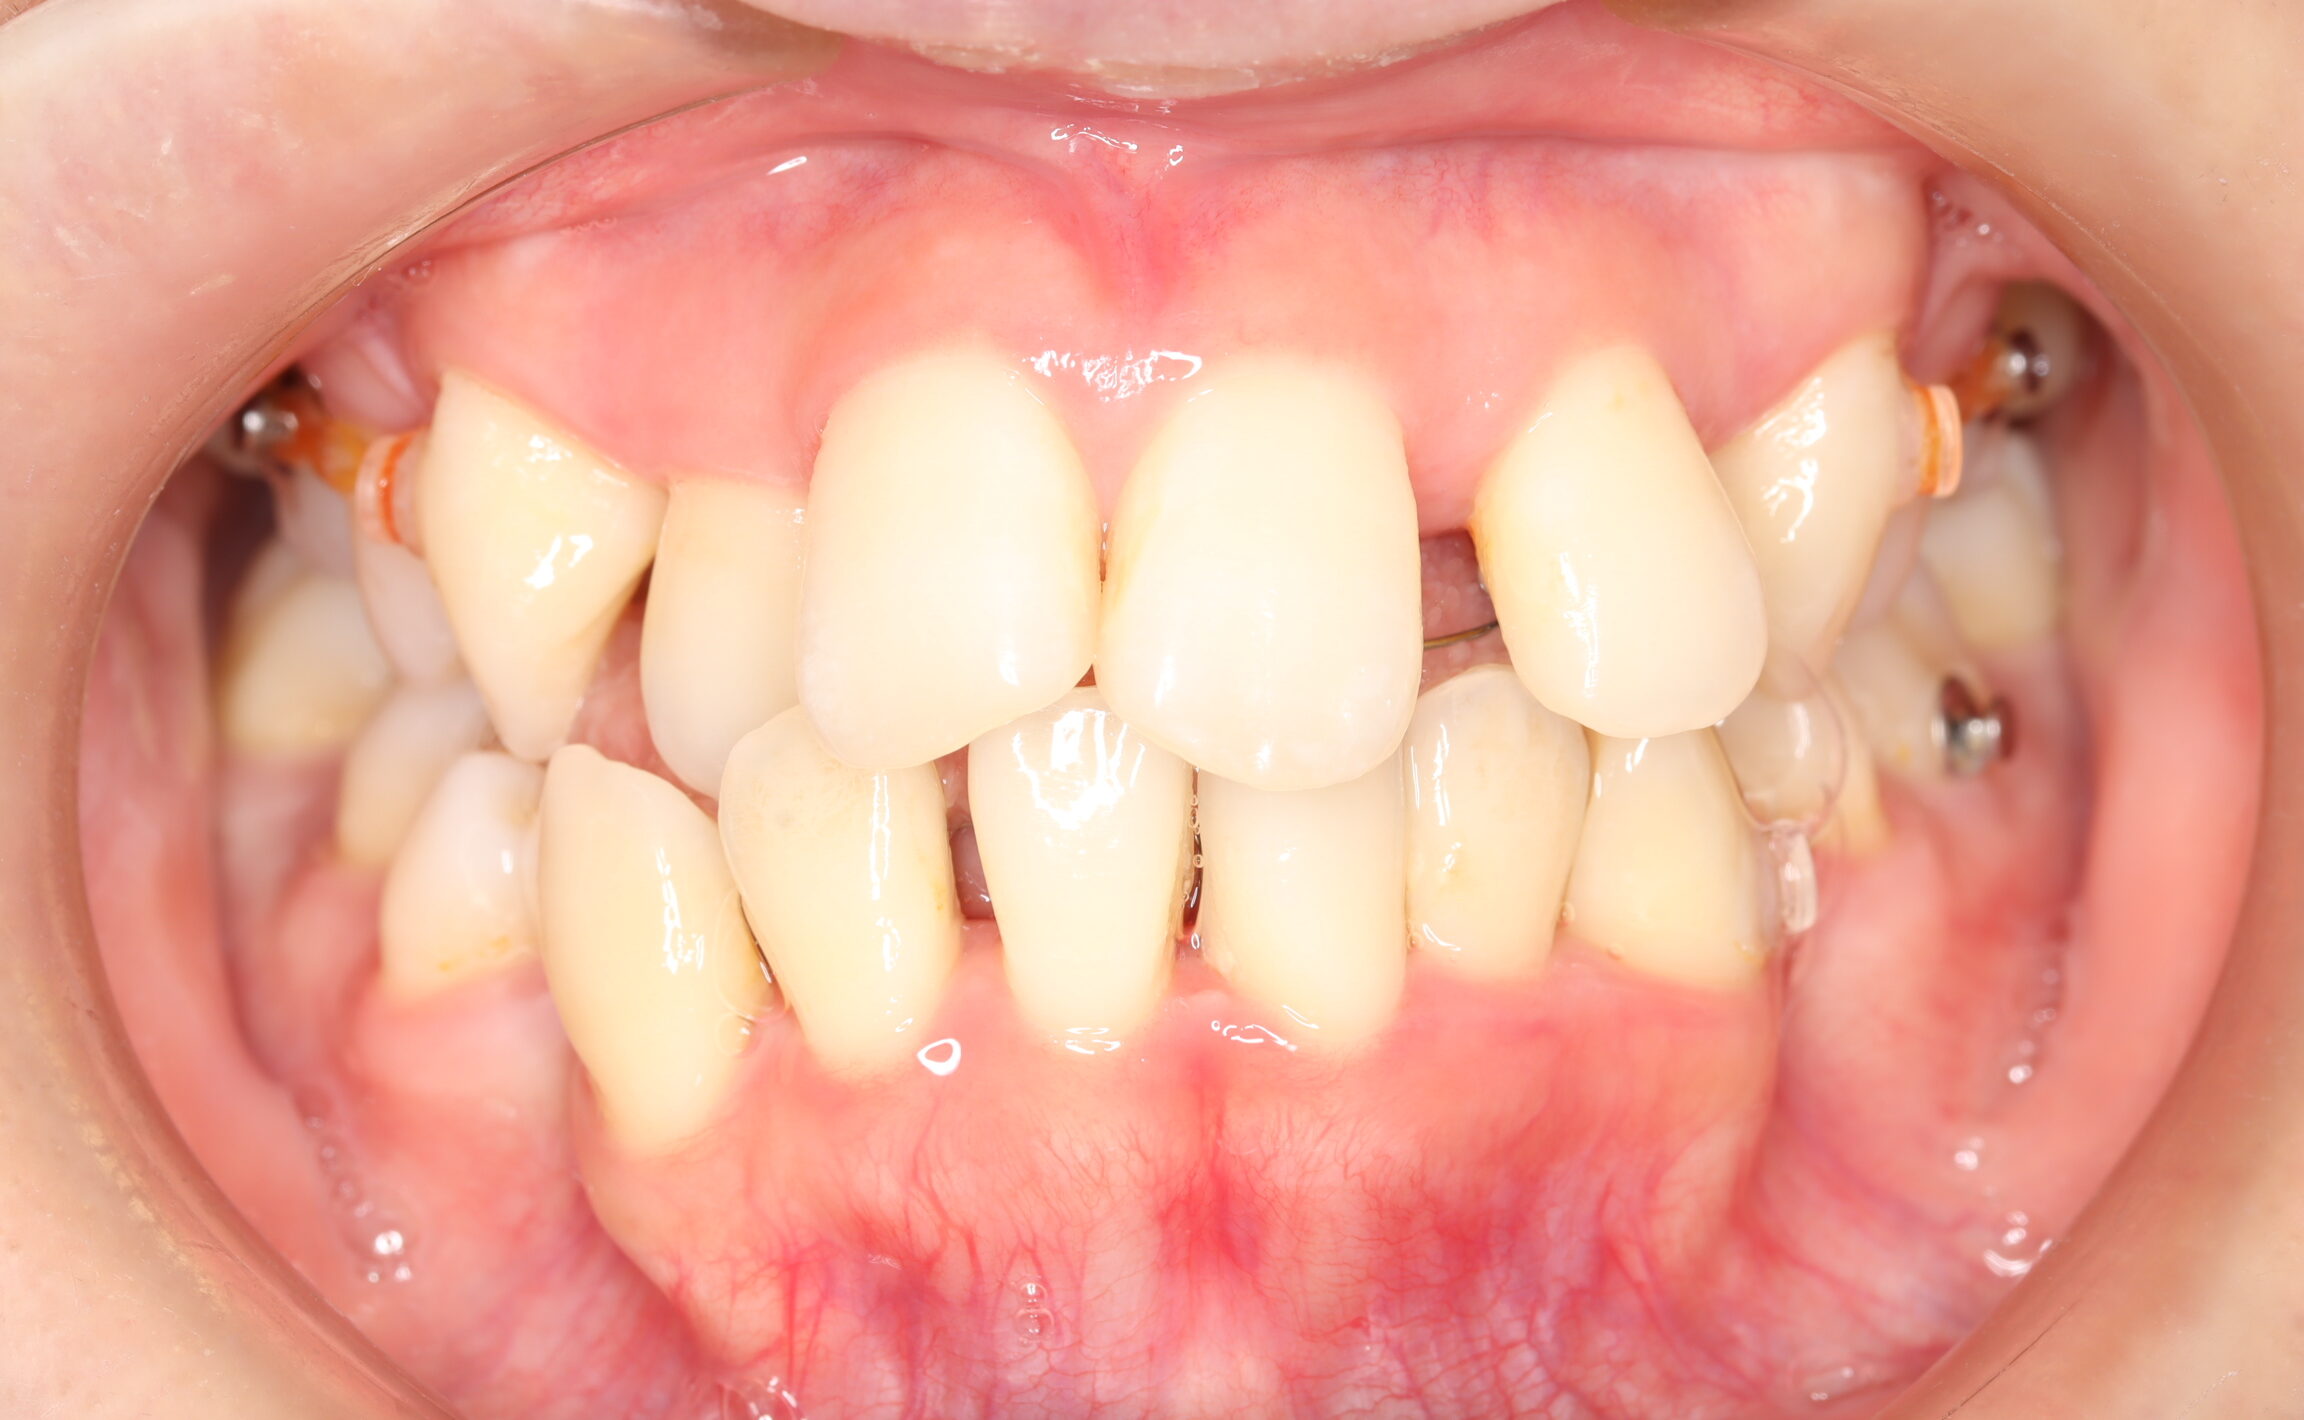

| 治療前 | SNSなどで「ガチャ歯」と呼ばれている、見た目のがたつきを治したかった患者さんです。 骨格的な問題はありませんでしたが、上下の前歯が唇側傾斜しており、上下顎前突症で口元の突出感がありました。 |

| 治療後 | 前歯から奥歯まで全体的に緊密な咬み合わせになっています。 歯のガタつきが無くなることにより、綺麗な見た目と歯磨きのしやすい口腔内環境になりました。 また突出感のあった口元もすっきりして綺麗なEラインとなり横顔も変化しました。 しっかりとしたかみ合わせを作ることにより、綺麗な歯並びになります。 |